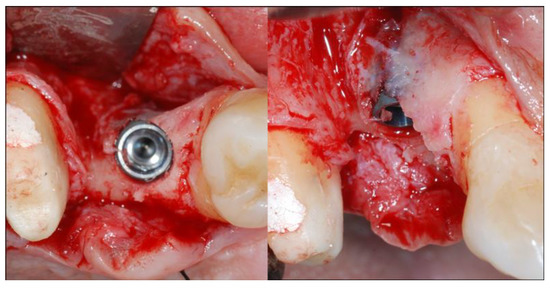

2.4. Surgical Phases

2.5. Re-Entry Surgery and Prosthetic Phases